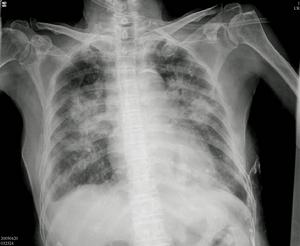

四、X線檢查 肺部多處小片狀浸潤陰影體勢膿毒性肺栓塞所致肺炎。左心衰竭時有肺淤血或肺水腫征。主動脈細菌性動脈瘤可致主動脈增寬。細菌性動脈瘤有時需經血管造影診斷。此掃描有助於腦梗死、膿腫和出血的診斷。